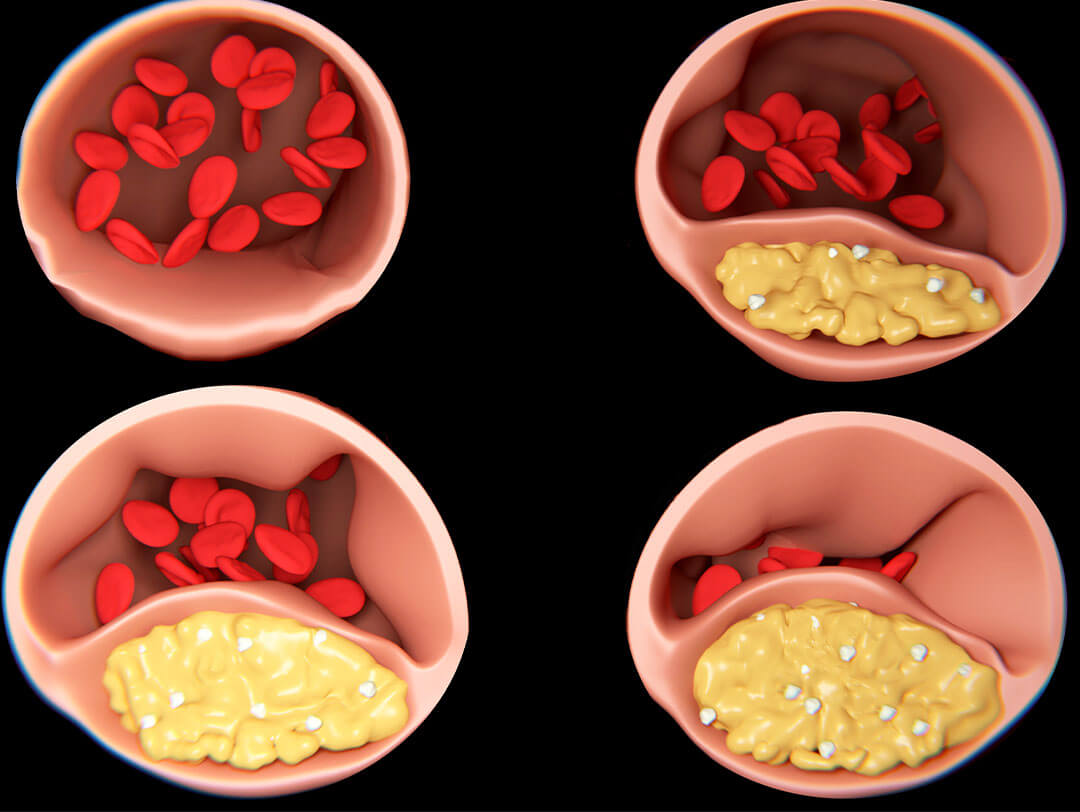

Eén van de belangrijkste oorzaken van de afvalbarrière is de slechte bloedcirculatie die optreedt tijdens de menopauze.

Oestrogeen – het belangrijkste vrouwelijke geslachtshormoon, waarvan de niveaus snel afnemen in deze periode – speelt hier een centrale rol.

Hoe dalende oestrogeenspiegels je gewrichten remmen

Oestrogeen houdt de bloedvaten elastisch:

Normaal gesproken zorgt oestrogeen ervoor dat je bloedvaten soepel blijven en dat het bloed vrijelijk kan stromen.

Als deze ondersteuning ontbreekt, worden de bloedvaten stijver en vermindert de bloedcirculatie.

Minder bloed betekent minder zuurstof en voedingsstoffen die de gewrichten bereiken – ze “verhongeren” letterlijk.

De kettingreactie van de afvalbarrière

Wanneer de hormoonbalans uit balans is, wordt een kettingreactie in gang gezet die de afvalbarrière verder versterkt:

Dalende oestrogeenspiegels:

Oestrogeen beschermt het kraakbeen door vocht vast te houden en de gewrichten soepel te houden. Zonder deze ondersteuning droogt het kraakbeen uit, wordt het gevoeliger voor stress, en is het minder goed in staat schade te herstellen.

Verhoogde ontstekingsgevoeligheid:

Hormonale schommelingen bevorderen ontstekingen, die vooral in de gewrichten voorkomen. Deze ontstekingsprocessen vallen het reeds verzwakte kraakbeen aan en veroorzaken pijn en extra slijtage.

Vertraagde stofwisseling:

Met het ouder worden, vertraagt de stofwisseling, maar de menopauze verergert dit effect aanzienlijk. Afvalproducten die normaal gesproken snel worden geëlimineerd, hopen zich op en bevorderen ontstekingen.

Gebrek aan drainage:

Door een slechte bloedsomloop en een vertraagde lymfestroom komen ontstekingsstoffen en afvalproducten vast te zitten in de gewrichten. Dit verhoogt de ontsteking en belemmert het natuurlijke herstel.